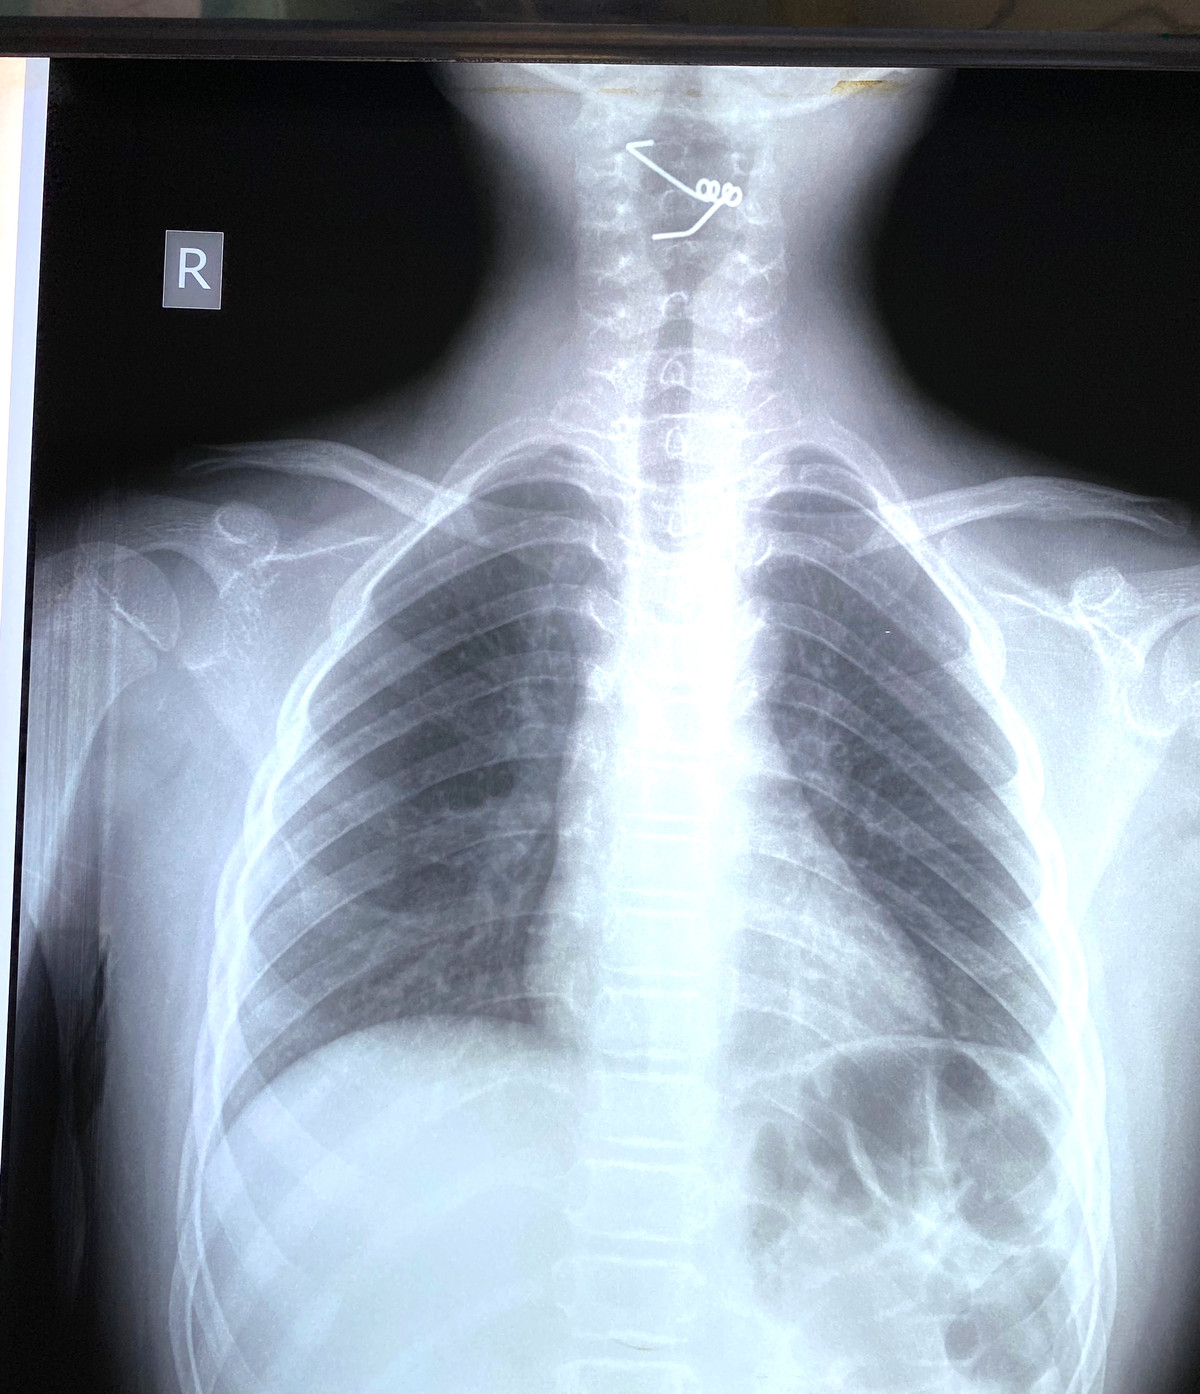

Bệnh nhi nam Lê Trần D M (9 tuổi, quận 3) nhập viện vì đau họng, vướng họng, không khó thở thanh quản, không ghi nhận hội chứng xâm nhập.

Soi hạ họng bằng ống soi treo thanh quản kiểm tra thấy dị vật là lò xo sắt có 2 càng. Chiều dài mỗi càng lò xo 3cm, 1 càng bị cài ở thành sau họng, 1 càng ở thanh thiệt.

Đây là một dị vật khá khó lấy vì các càng bám vào các cơ ở cổ. Sau lấy dị vật, niêm mạc của trẻ bị trầy xước ở thành sau họng và thanh thiệt.